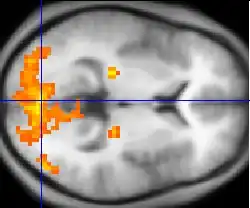

Differences in measured brain activity can be represented in various ways.

They can be presented as a table, displaying coordinates that show the most significant differences in activity between tasks. Alternatively, differences in brain activity can be shown as patches of colour on a brain 'slice', with the colours representing the location of voxels with statistically significant differences between conditions. The color gradient is mapped to statistical values, such as t-values or z-scores. This creates an intuitive and visually appealing map of the relative statistical strength of a given area.

Differences in activity can be represented as a 'glass brain', a representation of three outline views of the brain as if it were transparent. Only the patches of activation are visible as areas of shading. This is useful as a means of summarizing the total area of significant change in a given statistical comparison.